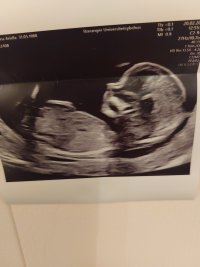

Nub teorien går ut på å gjette kjønnet ut i fra vinkelen "nuben" står i. Gutte-nub står mer opp og gjør det allerede fra uke 11-12. Jente-nub ligger mer flatt ned.

Så hvis noen har ultralydbilder fra uke 12 og utover de ønsker en tolkning på så legg gjerne inn her.Jeg har mange års erfaring med nub teorien og elsker å gjette kjønn

Litt uklart bilde, men tipper gutt. Det jeg tror er nub har litt høy vinkel til å være jente. Har du flere bilder i andre vinkler?Lyst til å gjette?Bilde fra uke 13+0. Vet ikke om nuben synes så godt men

Litt uklart bilde, men tipper gutt. Det jeg tror er nub har litt høy vinkel til å være jente. Har du flere bilder i andre vinkler?